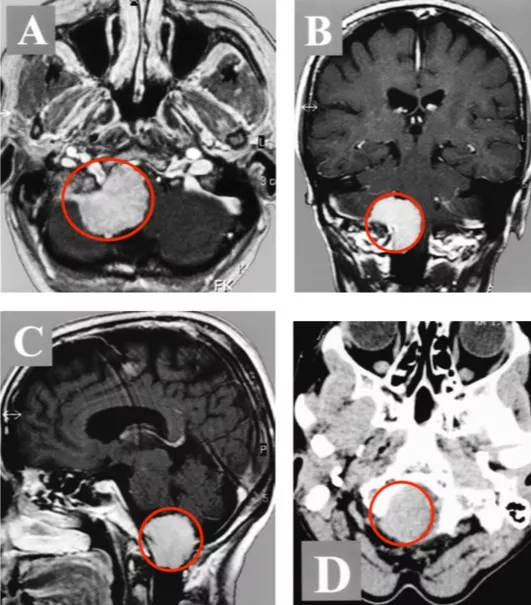

57岁女士,以颈部疼痛、走路乏力、步态紊乱发病。术前影像显示右侧较大的前外侧占位,并且体积已经发展到大了,下脑干在枕骨大孔处被较大限度地压缩,肿瘤占据了90%以上的可用空间。

INC国际神经外科顾问团成员、国际神经外科联合会(WFNS)教育委员会主席德国Helmut Bertalanffy(巴特朗菲)教授采取了左侧卧位,让患者置于左侧侧位,头部弯曲并旋转到右侧。手术术中应用躯体感觉和听觉诱发电位的连续监测。侧枕下开颅术延伸至远侧乙状窦和C1半椎板切除术,枕骨大孔的背外侧边缘逐渐被钻开,并对脑干和脊髓进行了精心护理。

术后CT和MR,显示肿瘤及其被肿瘤侵犯的骨质都切除,肿瘤全切,Simpson一级切除。术后患者没有新发神经功能缺损,患者在术后二天开始肢体活动,轻微的颈部疼痛,并很快好转、消失。没有相关手术并发症,特别是没有脑脊液漏出或脊柱不稳定。术后计算机断层扫描(CT)和磁共振成像(MRI)分别显示了部分骨切除和肿瘤全切,术后伤口美观。患者肿瘤全切,未行放化疗等,术后12年未见复发,生活如常,对效果很满意。